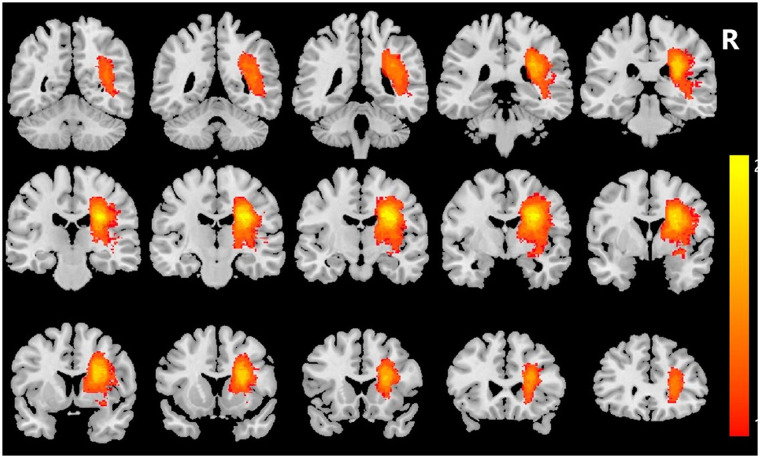

BackgroundThe cerebellar cortex has gradually become a promising therapeutic target for improving motor recovery post-cerebral infarction, potentially dependent on the structural integrity of motor-related corticocerebellar pathways (CCP). However, the relationship between the imaging markers of motor-related CCP and motor prognosis remains inadequately explored. Utilizing diffusion tensor imaging (DTI), this study aims to longitudinally assess the role of motor-related CCP in predicting motor recovery for both upper and lower extremities following cerebral infarction.MethodsTwenty-nine patients with right middle cerebral artery (MCA) infarction underwent 2 DTI scans 7 to 14 and 30 days after onset, and 29 age-sex matched controls received 1 scan. Fractional anisotropy (FA) values were measured for corticospinal tract (CST) and CCP (cortico-pontocerebellar tract, CPCT; dentate-thalamocortical tract, DTCT; dorsal-spinocerebellar tract, DSCT). Multivariate regression analyses were performed to examine the relationships between DTI parameters and Fugl-Meyer Assessment (FMA).ResultsCompared to the control group, FA and FA asymmetry index (FA-AI) of CST, DTCT, and DSCT on the affected side were significantly reduced. In the linear regression model, the decreased FA-AI of DTCT was a strong predictor for upper FMA (R2adj = 0.271, P = .022), while the FA-AI of DSCT independently predicted lower limb FMA (R2adj = 0.400, P = .019).ConclusionsIn patients of MCA infarction, FA-AI of motor-related CCP may be a valuable imaging indicator for predicting motor outcomes. The DTI-assessed structural integrity of the cerebellar ascending fiber tracts (DTCT and DSCT) may correlate with the motor recovery of the upper and lower extremities, respectively.

Abstract Image